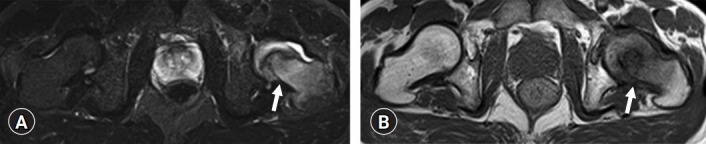

Fig. 6.

Magnetic resonance imaging (MRI) axial view of the left femoral neck fracture (arrows). MRI shows a clear fracture line in the left femoral neck. (A) Short tau inversion recovery image. (B) T1-weighted image.